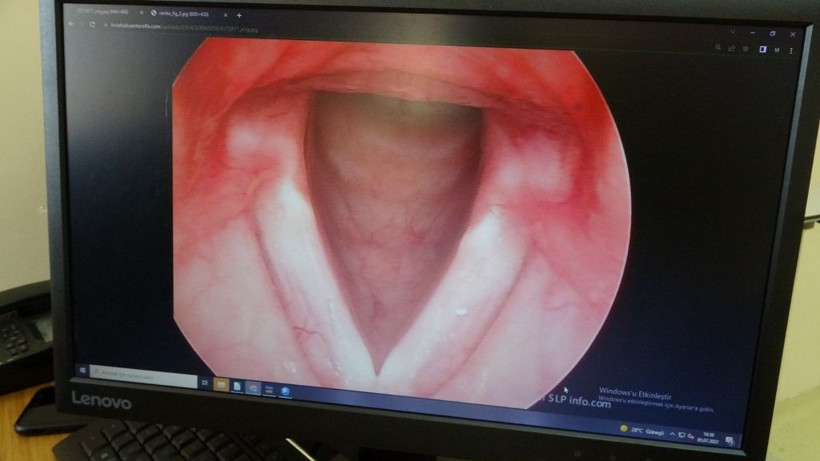

Sigaranın saymakla bitmeyen zararlarının yanı sıra çok az bilinen bazı kötü yönleri de bulunuyor. Sigaranın zararları ile ilgili açıklamalarda bulunan Kulak Burun Boğaz Hastalıkları ve Baş Boyun Cerrahisi Uzmanı Doç. Dr. Necati Enver, sigaranın ses tellerindeki kalıcı hasarlarını dile getirdi.

Özellikle kadınların ses tellerinde daha çok etki gösteren sigara, önlem alınmadığı veya içmeye devam edildiği takdirde tehlikeli sonuçlara gebe olabiliyor.

Sigara kullanımı insanlarda birçok olumsuz etkiyi beraberinde getiriyor. Çeşitli hastalıkların yanı sıra sigara kullananlarda ses kısıklığı da meydana gelebiliyor. Bu problem nedeniyle seste kalınlaşma, sesin cızırtılı gelmesi, sesin kolay yorulması, boğuk ve zor duyulur bir ses gibi belirtiler görülebiliyor. Zarar gören ses tellerinde poliplerin ve ödemlerin oluşmasıyla meydana gelen ses kısıklığı nedeniyle ileri safhalarda nefes darlığı ve konuşmakta ciddi güçlükler de oluşabiliyor. Bu rahatsızlığı geçiren kadınlarda ise ses kalınlaşması oluşabiliyor.

Hastalar, seslerinin erkek sesi gibi kalın olmasından ve telefonda konuştukları kişinin kendilerini erkek sanmaları gibi nedenlerden dolayı hastanelere başvurabiliyor. Oluşan bu rahatsızlık ise kısa süren bir ameliyat ile tedavi edilebiliyor.

Kulak Burun Boğaz Hastalıkları ve Baş Boyun Cerrahisi Uzmanı Doç. Dr. Necati Enver, tedavinin hastalar açısından kolay olduğunu ve sesin yaklaşık 1 hafta sonra kullanılabildiğini belirtti.